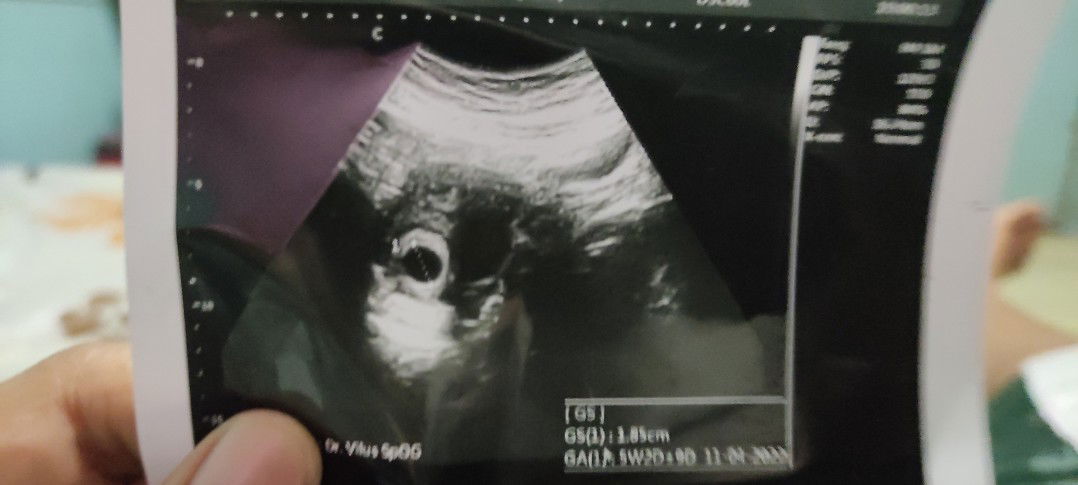

Doain ya bun,jam 2 ni sya di kuret bunπβΉοΈ Belom rejeki kami bundaπ’

sabar ya saya tau perasaan nya. saya juga riwayat kuret plonga-plongo diruangan inap ngga ada bayi.